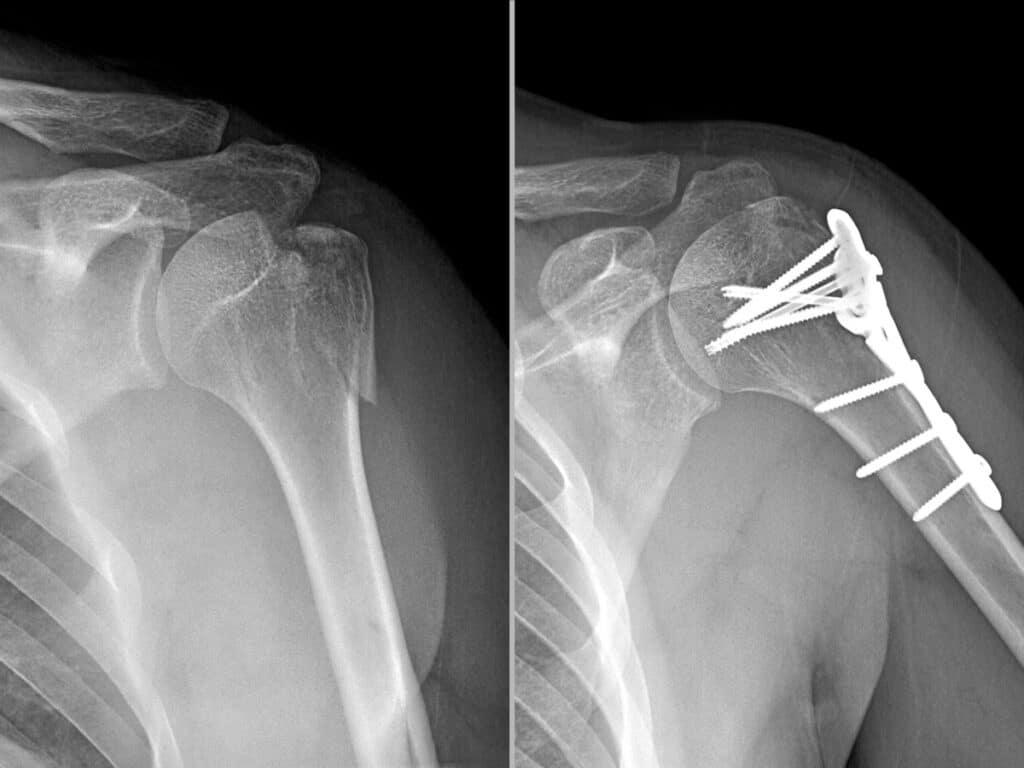

ادامه مطلبپس از تشخیص شکسته شدن شانه از طریق اشعه ایکس، بازوی شما به طور معمول از طریق مچ دست در یک اسلینگ پشتیبانی میشود. اسلینگ اجازه میدهد تا وزن بازو، استخوان بازو را به سمت پایین بکشد. نیروی جاذبه رو به پایین به بهبود استخوانهای شکسته در موقعیت صحیح کمک میکند. درمان شانه شکسته با…